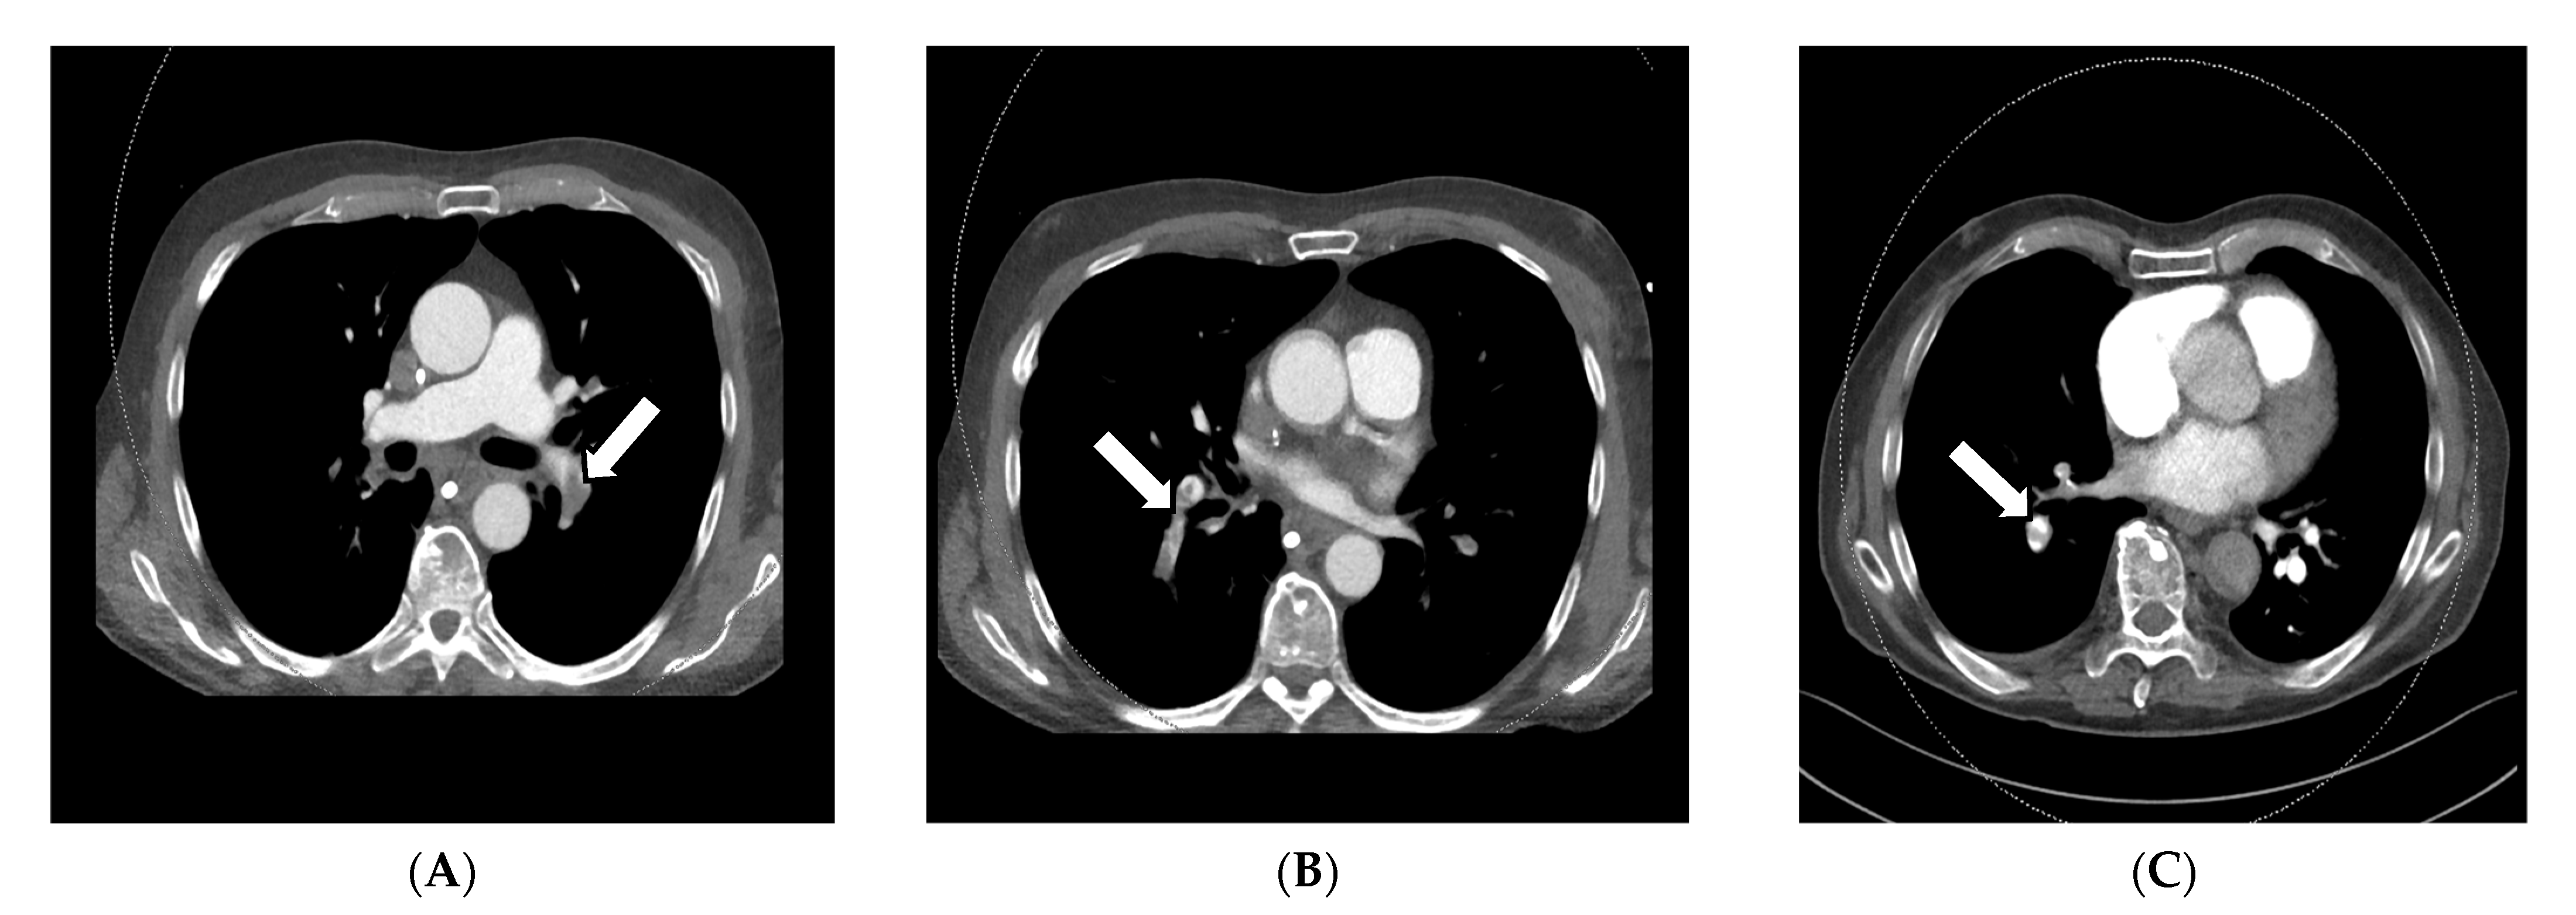

For diagnosing pulmonary embolism, iodine mapping, and perfusion analysis are advantageous features for the visualization of hypoperfused areas, usually V-shaped areas in the perfusion maps, which can be used as a colored overlay map on anatomic CT reconstructions according to Thieme et al., 2008 and many other publications. This semi-quantitative technique allows for relative measurements of iodine uptake in the lung parenchyma (See Figure 2A–D) [31,33,34,37,38,41].

Figure 2.

Application of iodine mappings and perfusion visualization facilitating DECT in a DSCT scan of a 23-year-old woman suffering from chest pain, tachycardia, and dyspnea. The 50 kV axial soft tissue kernel reconstruction CT angiography of the pulmonary arteries showed central thrombosis of both main pulmonary arteries on the right side (A,B) and the left side (C) with partial occlusion of the subsequent vessels. V-shaped perfusion deficits were reported in the perfusion maps (D,E), which can be correlated to segments 9/10. In correspondence to the missing contrast agent in the responding segmental arteries of these segments, a total occlusion was suspected. The patient was accordingly treated with systemic anticoagulation.